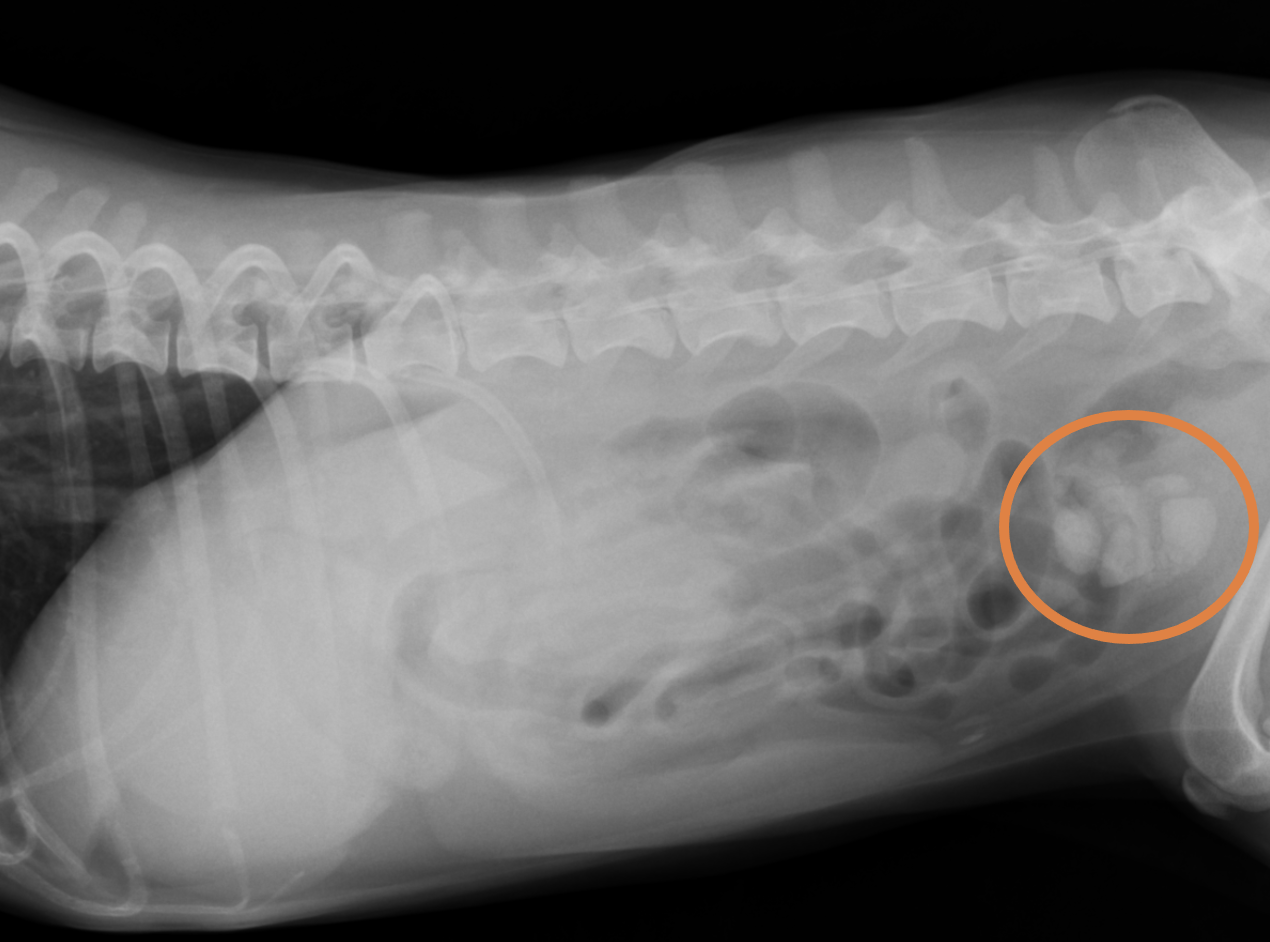

12歳、女の子のわんちゃんです。血尿と嘔吐、排尿姿勢をとるものの尿が出てこない、を主訴に来院されました。各種検査を行いましたが、レントゲン検査により、膀胱内に結石が複数個確認されました。下のレントゲン画像に示すとおり、膀胱の中に1cm程度の白い構造物が見えます。

その際は内科療法により良化しました。しかし、10ヶ月後に、4日間ご飯を食べず尿をそこら中でしてしまうという主訴で再び来院しました。レントゲン検査の結果、2cm程度の結石が確認されました。下の画像がレントゲン画像になります。以前は1cmだった結石が、たった10ヶ月の間に2倍の大きさになっていました。結石が大きくなる時間は結晶の種類や尿の性状などにより様々ですが、このように急速に大きくなり、激しい症状を出してしまう場合もあります。この子は膀胱切開術の手術により膀胱内の結石を摘出し、治療した結果完治しました。下に示す写真は結石摘出前後のレントゲン画像と、摘出した結石の一つです(残りは結石分析に提出しました)。